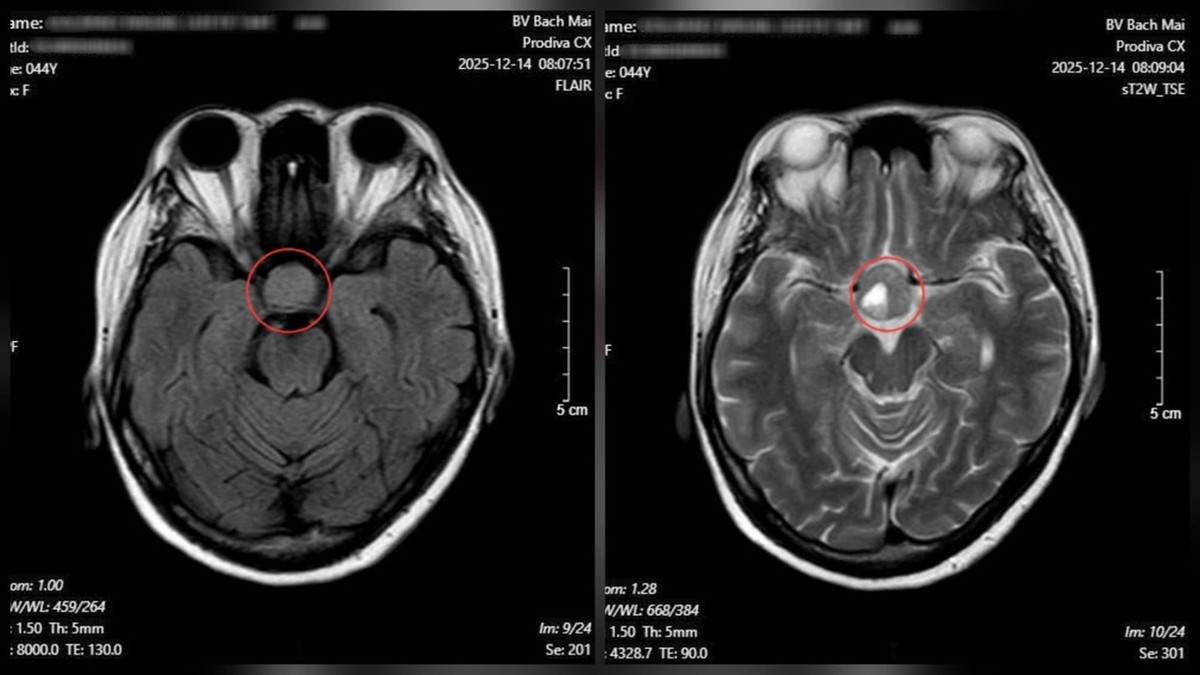

Từ những dấu hiệu trên, bệnh nhân được chỉ định chụp cộng hưởng từ (MRI) sọ não. Kết quả cho thấy một khối u tuyến yên kích thước lớn (macroadenoma), kích thước 26 × 21 mm.

Kết quả chụp cộng hưởng từ (MRI) sọ não cho thấy một khối u tuyến yên kích thước lớn - Ảnh BVCC